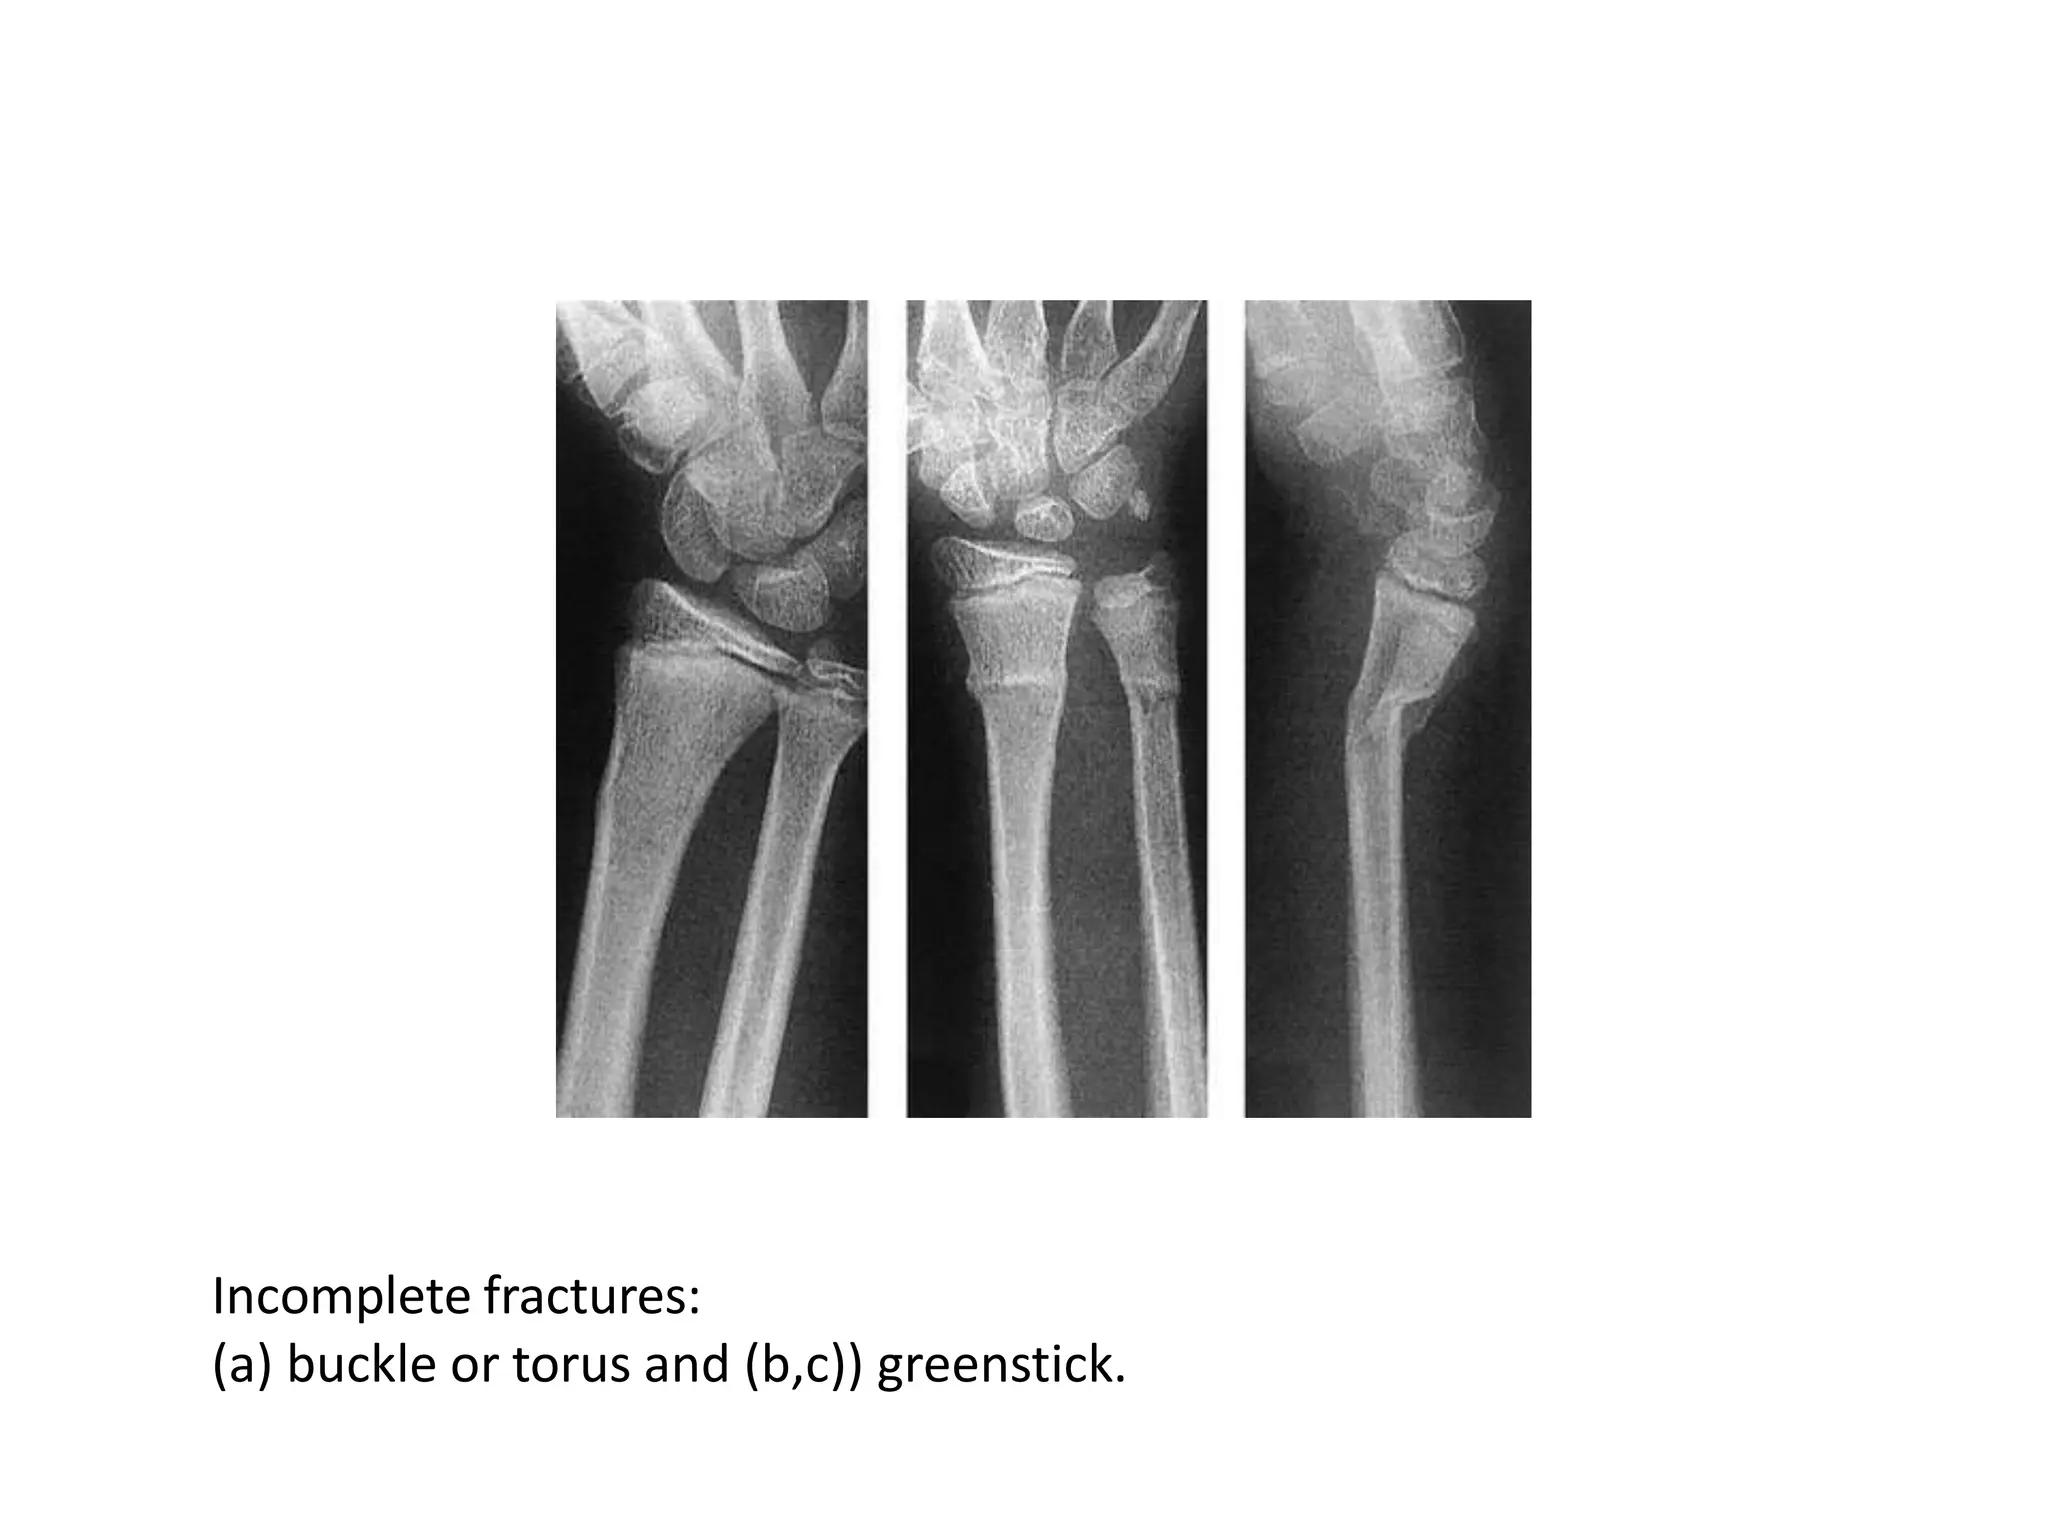

Incomplete fracture

• The bone is incompletely divided and the

periosteum remains in continuity

• Greenstick fracture : bone is buckled or bent

– Mainly seen in children, because of their springy

bones

– Plastically deformed bones

• Compressed fracture: crumpled cancellous bone

– Seen in adults, mainly in vertebral bodies, calcaneum

and tibial plateu

Incomplete fractures:

(a) buckle or torus and (b,c)) greenstick.

Incomplete fractures: (a) buckleor torus and (b,c)) greenstick.